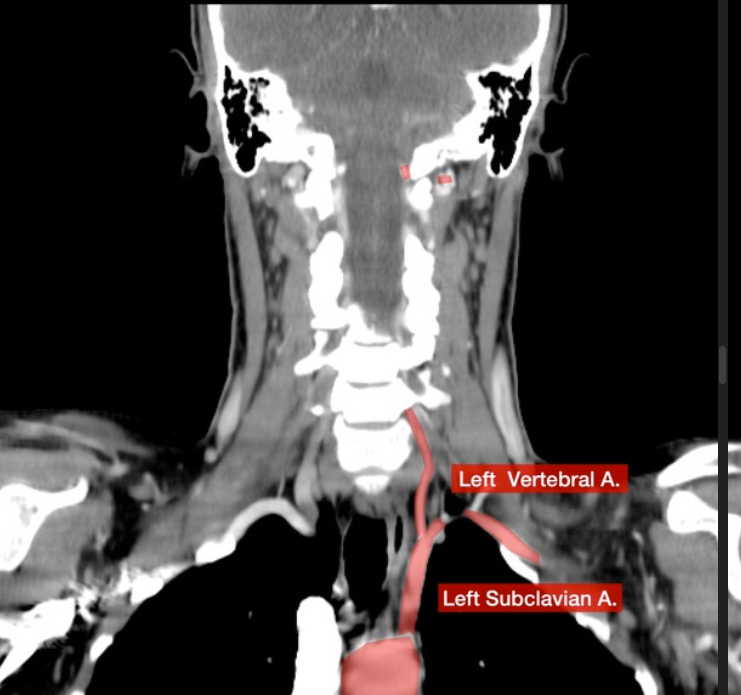

Label the arteries